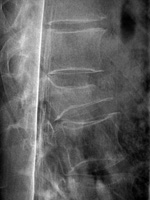

| Lumbar spine bony disk strut, pedicle screws, and pedicle rods (AP view) |

Lumbar spine bony disk strut, pedicle screws, and pedicle rods (lateral view) |

| There is an anterior allograft bone strut used to treat metastatic neuroblastoma in the L4 vertebral body. The bone strut crosses both the pathologic vertebral body as well as its adjacent disk. The anterior position of the bone strut is typical for these struts. From Hunter, 2004 |